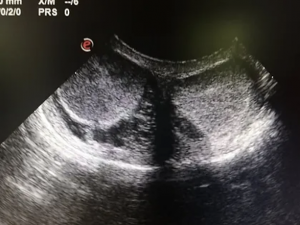

Pri majhnih pasmah (do 10 kg odrasle teže) je idealna starost za kastracijo od 6 mesecev dalje. Srednje velike pse (10–20 kg) običajno kastriramo med 6. in 8. mesecem starosti. Pri velikih in zelo velikih pasmah (nad 20 kg) pa je priporočljivo počakati do telesne zrelosti, kar je med 10. in 18. mesecem. Prezgodnja kastracija pri večjih psih se odsvetuje, saj lahko negativno vpliva na njihov razvoj in rast. Zgornje starostne meje za kastracijo ni. Pri starejših psih je najpogostejši razlog za poseg povečana prostata. Statistični podatki kažejo, da ima kar večina psov po šestem letu starosti benigno povečano prostato, po devetem letu pa spremembe zaznamo pri skoraj vseh psih. Čeprav se lahko določene utrjene vedenjske navade, kot so potepanje in markiranje, po kastraciji delno omilijo, je pri odraslih psih pogosto potrebna tudi dodatna prevzgoja.

Pred posegom se je treba naročiti pri veterinarju, ki vas bo seznanil z vsemi pomembnimi informacijami. Pojasnil vam bo, kako pripraviti psa na operacijo, na primer, da mora biti pred posegom tešč. Prav tako vas bo obvestil o uri prihoda in predvidenem času odpusta psa. Pred samo operacijo veterinar opravi osnovni klinični pregled psa, nato vam predstavi potek kirurškega posega ter opozori na morebitne zaplete. Če je pes zdrav, mu veterinar aplicira pomirjevalo, nakar običajno skupaj z vami počaka še 5–15 minut, da zdravilo začne delovati. Po tem veterinarska ekipa prevzame psa, ga uvede v splošno anestezijo in opravi kastracijo. Med operacijo naredijo rez na mošnji in odstranijo moda. Po zaključku posega psa skrbno nadzirajo, spremljajo njegovo stanje ter poskrbijo za ogrevanje, infuzijsko podporo in protibolečinsko terapijo. Psa praviloma odpustijo v domačo oskrbo še isti dan, skupaj z navodili za nego in okrevanje.